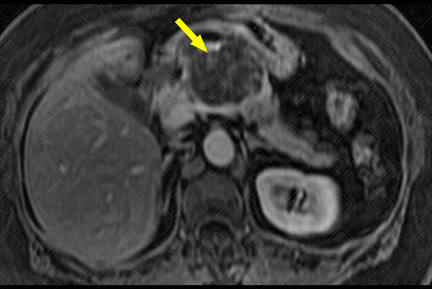

Texto alternativo para a imagem Figura 2. Créditos: Dra. Elazir Mota - Rio de Janeiro/RJ

Descrição da figura 2: Sequência T1, pós-contraste, plano axial, evidenciando a mesma lesão, com realce pós-contraste da parede dos septos, no interior da lesão (seta amarela).